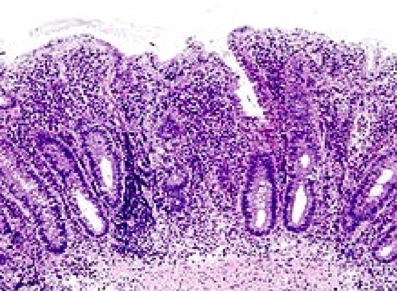

Inpatient colonoscopy was performed, during which erythema congestion and ulceration in the rectum, sigmoid colon, and descending colon were found (Figure 1). Biopsies were taken. On histological examination, the rectal, sigmoid, and descending colon mucosa showed mucosal hyperplasia with crypt abscess and evidence of acute and chronic inflammation (Figure 2). A diagnosis of ulcerative colitis (UC) was made.

Figure 2. Histological examination showed mucosal hyperplasia with crypt abscess.